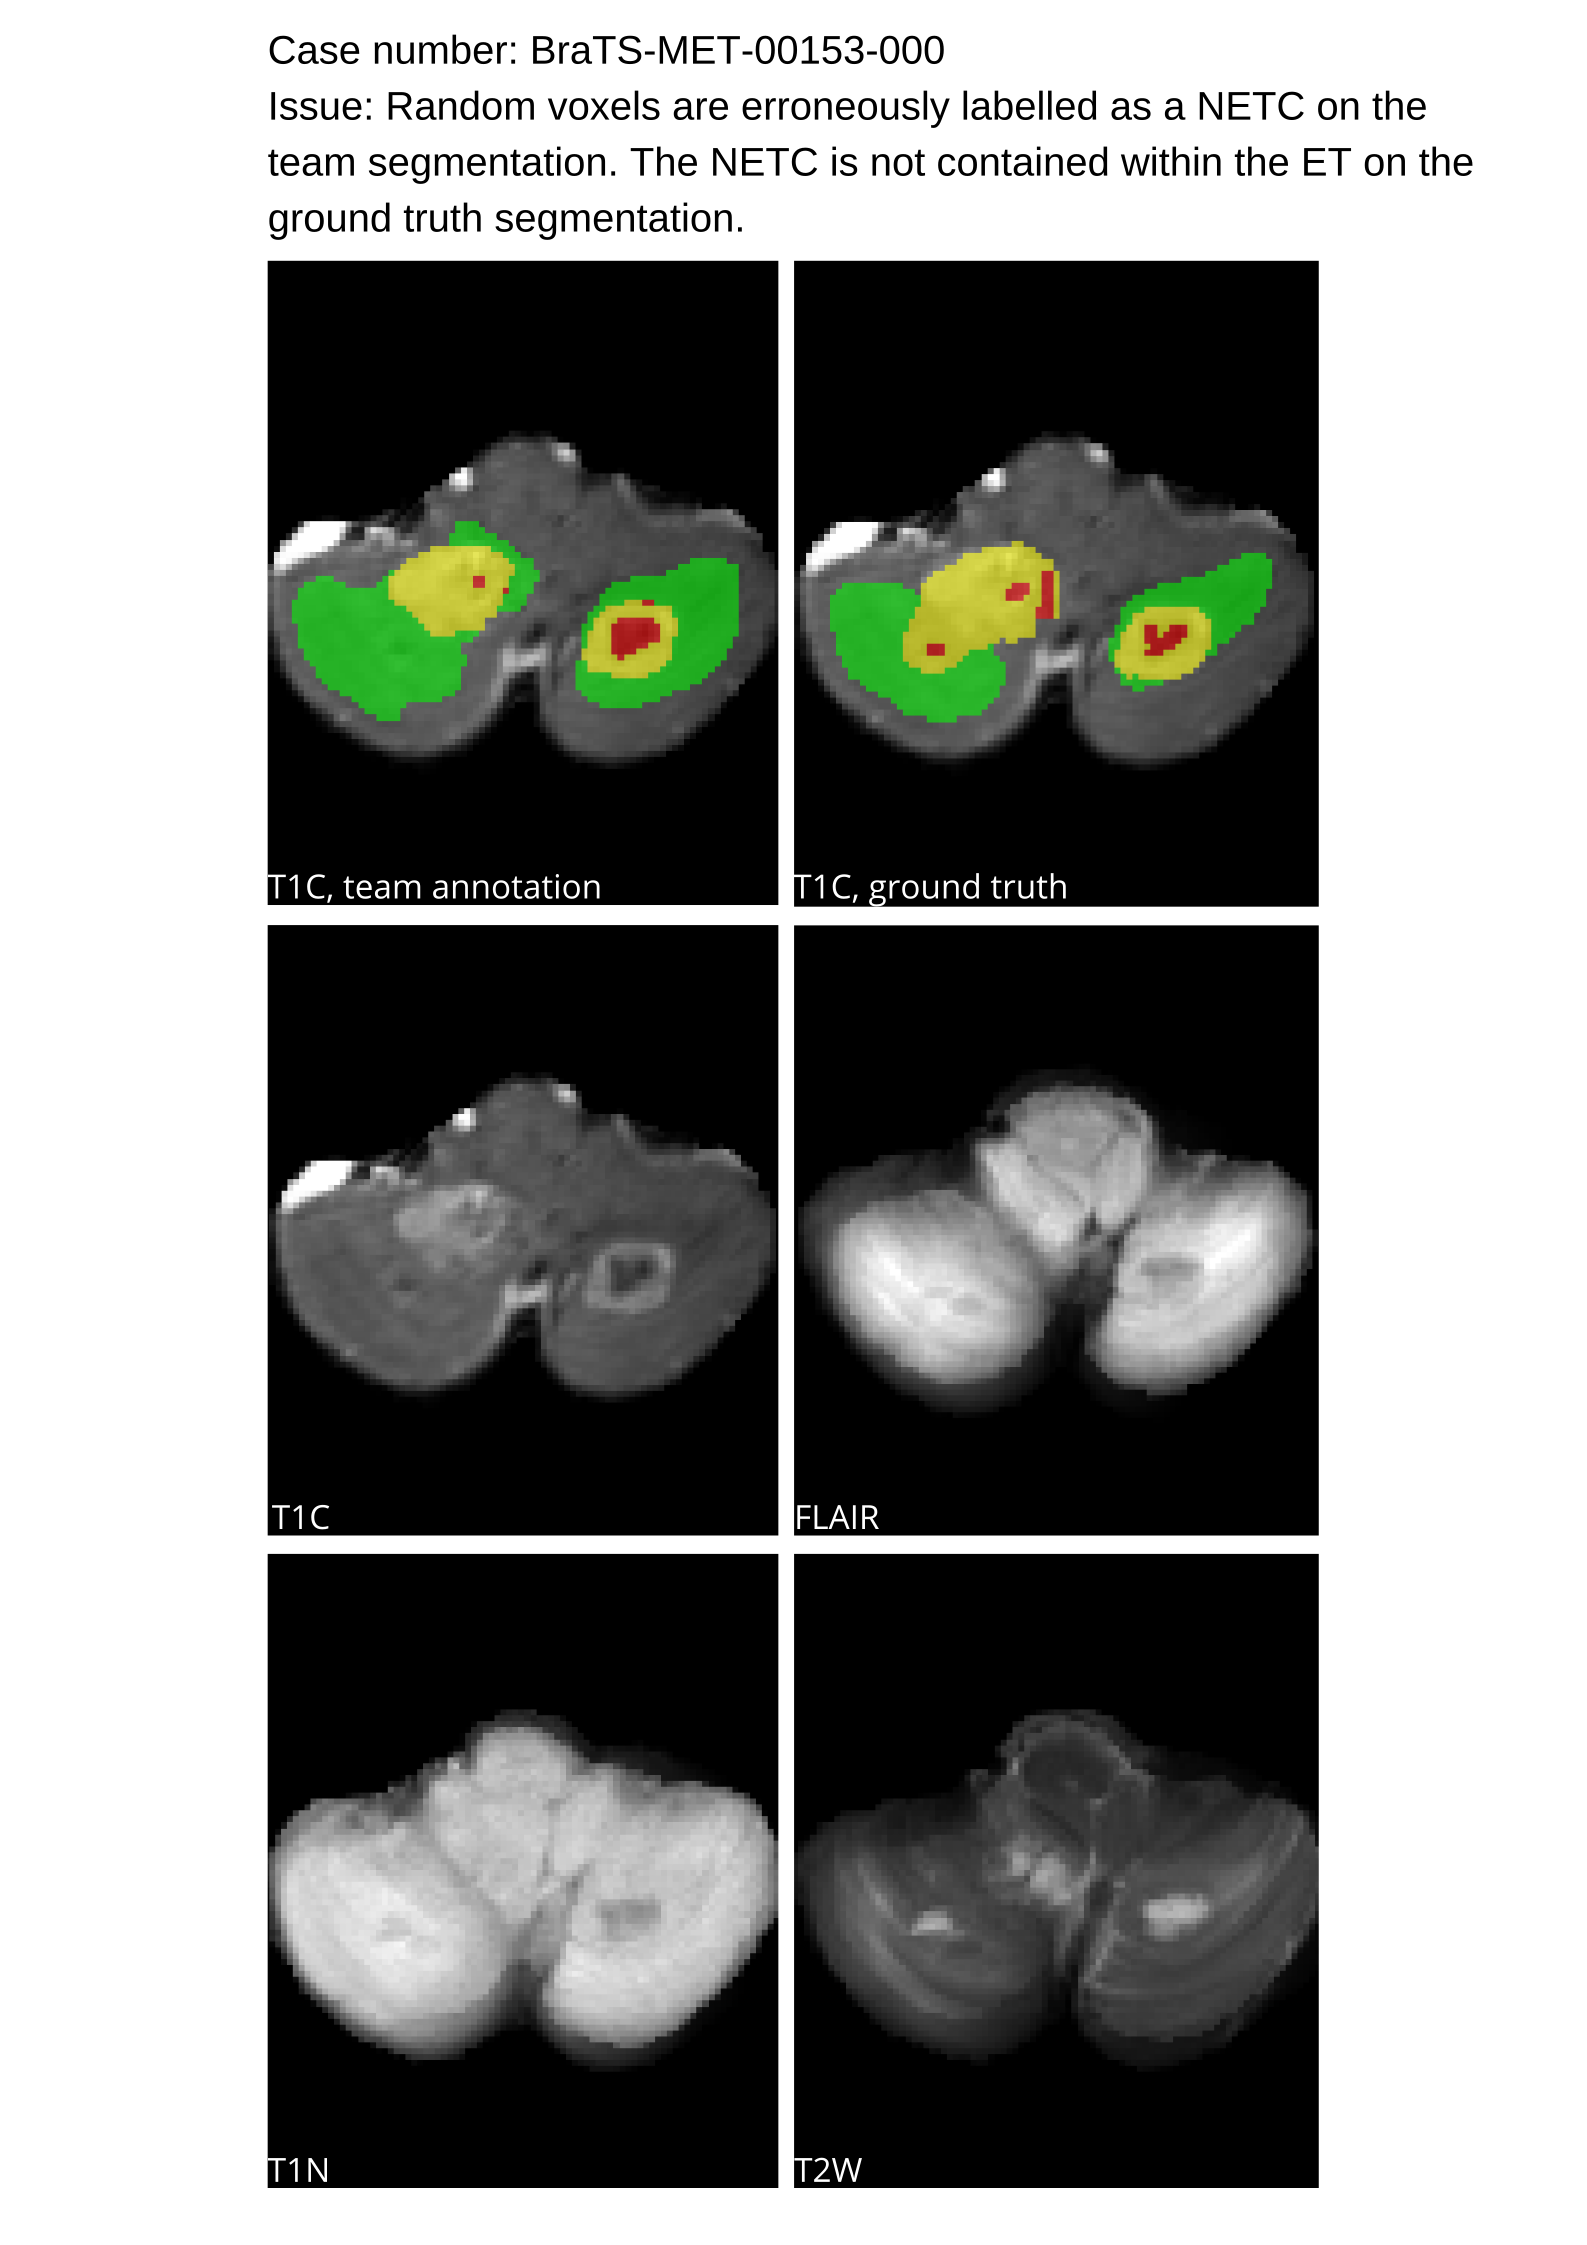

Approvers reviewed the volunteer annotations and either approved the case or returned it to students for re-annotation. Additionally, a QC process was implemented, which included removing all random voxels and any voxels outside the brain mask, ensuring all images had the same parameters (space, orientation, and origin) as the SRI24 atlas, and verifying the presence of all segmentations and segmentation masks are in the folder with original NIfTI images.

4.9 Common Errors of Automated Segmentations

Based on observations from previous BraTS challenges, common errors in automated segmentations were identified. The most typical errors in the current challenge included:

1. 1.

Automated algorithms missing small metastases. Enhancing metastasis was fused using the minority voting algorithm to aggregate all enhancing tumor voxels identified by the three algorithms. However, many small metastases were missed and were manually segmented by neuroradiology attendings.

2. 2.

Segmentation of white matter changes from microvascular disease. Peritumoral edema segmentations were checked by neuroradiology attendings and modified.

3. 3.

The segmentation of non-enhancing lesions that have intrinsic T1 hyperintensity. Voxels with intrinsic T1 hyperintensity were manually removed from ET segmentations.

These insights led to specific adjustments in the annotation process to enhance accuracy.